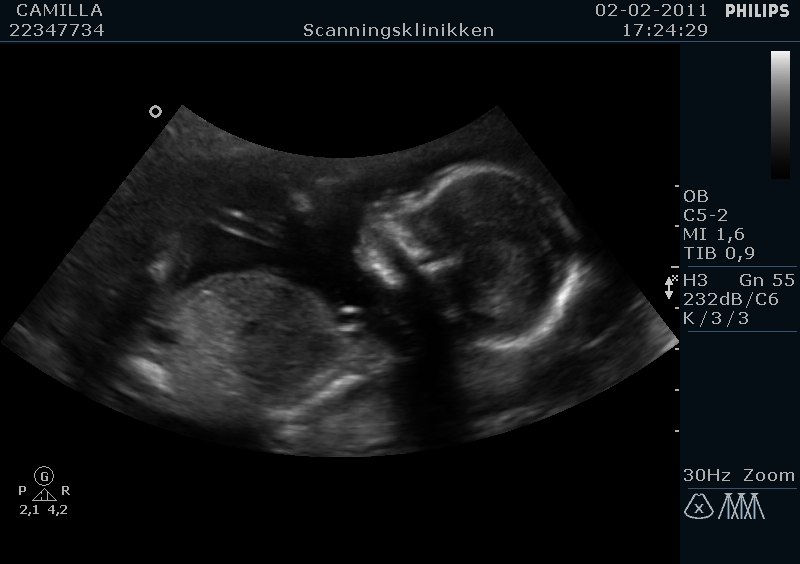

Hej alle sammen. Flertallet fik ret: Vi skal have en skøn lille dreng :-D :-D

Fik sgu tårer i øjnene da jeg fik øje på tappen! Så stort!

I får lige nogle billeder :-)

Tillykke med ham, hvor er det bare dejligt og hvor er han lille og fin på scanningsbillederne...

Ja er han ikke Vi fik hele 50 billeder på en cd rom, og så 5 stk i print